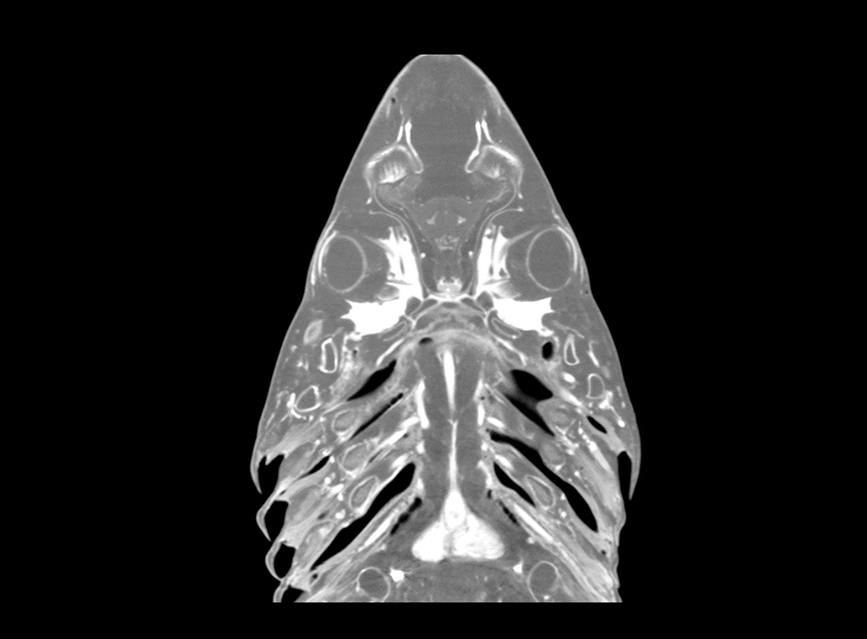

Our High Definition Volumetric Imaging (HDVI) technology is the most advanced form of Flat Panel CT technology. It delivers high-quality diagnostic imaging for both hard and soft tissues. This technology includes specific presets and customizable accessories designed for aquatic animals.

Outstanding image quality in hard and soft tissues with a spatial resolution up to 100 μ.